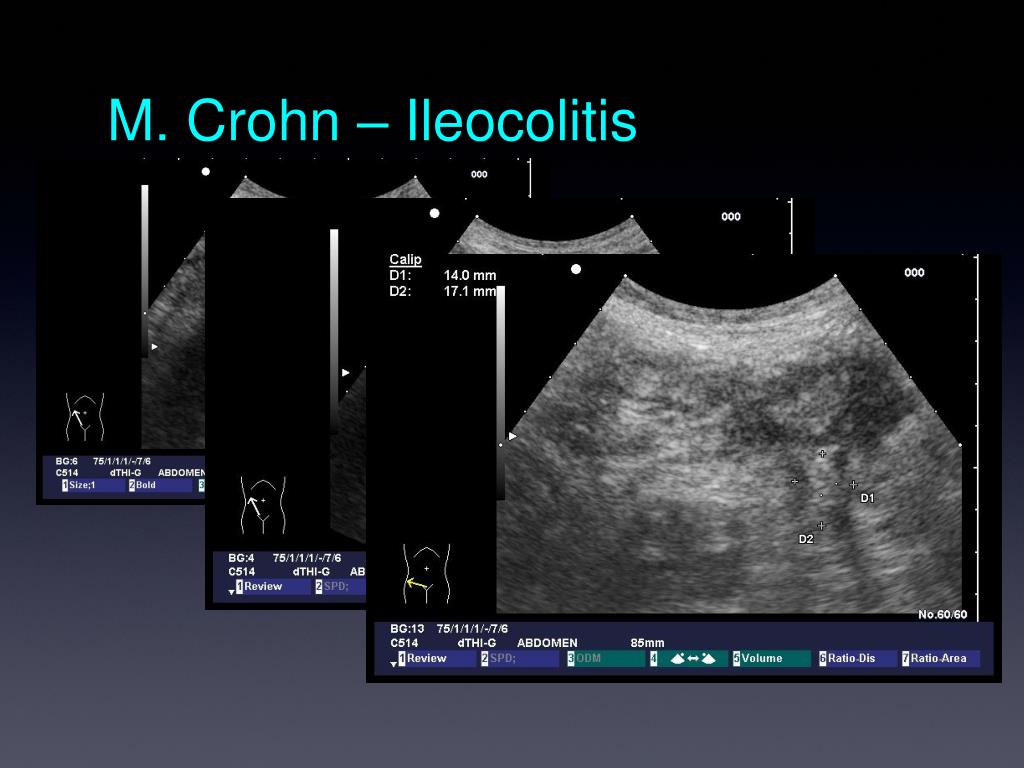

36. M. Crohn – Ileocolitis

28. Kolon – Normalbefund • Lumen mit Gas gefüllt • Durch Plicae in Haustren unterteilt • Schmale Darmwand vom stark reflektierendem Gas überstrahlt • Wandschichtung meist nicht erkennbar